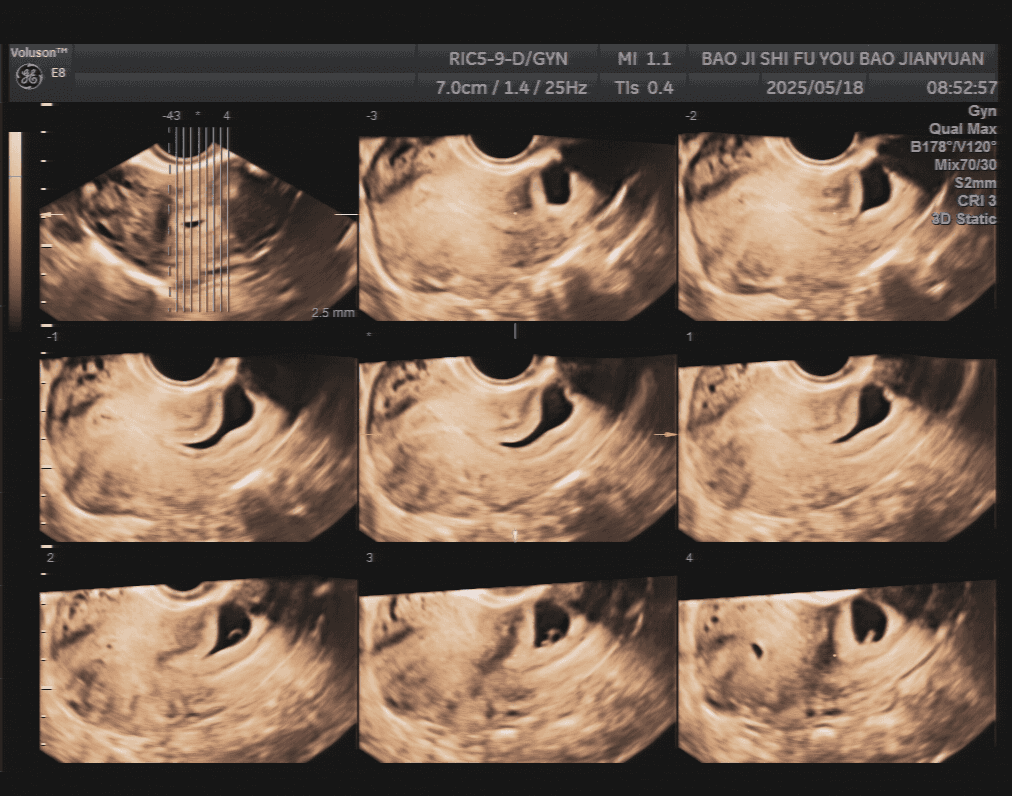

治疗前三维图

37岁的李女士(化名)便是这项技术的受益者。她停经43天,尿HCG检测呈阳性,在外院超声检查提示为:早孕且胚胎存活(瘢痕部妊娠Ⅱ型)。转入该院后,妇科主任张朝红为其安排了子宫三维超声检查,结果显示瘢痕部妊娠、胚芽存活(Ⅱ型),瘢痕部肌壁仅厚1.2mm,孕囊与瘢痕部间有丰富血流信号。